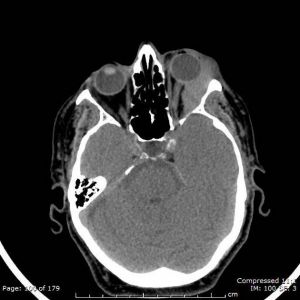

Radiology

Computed Tomography (CT): CT findings may commonly show a moderately well-defined homogeneous orbital mass molding to the adjacent ocular structures without bony involvement. Patterns of presentation include retroocular, anterior preseptal, lacrimal gland involvement, or extension of adnexal lesion. Higher grade lesions are associated with a more heterogeneous mass appearance with bony destruction.